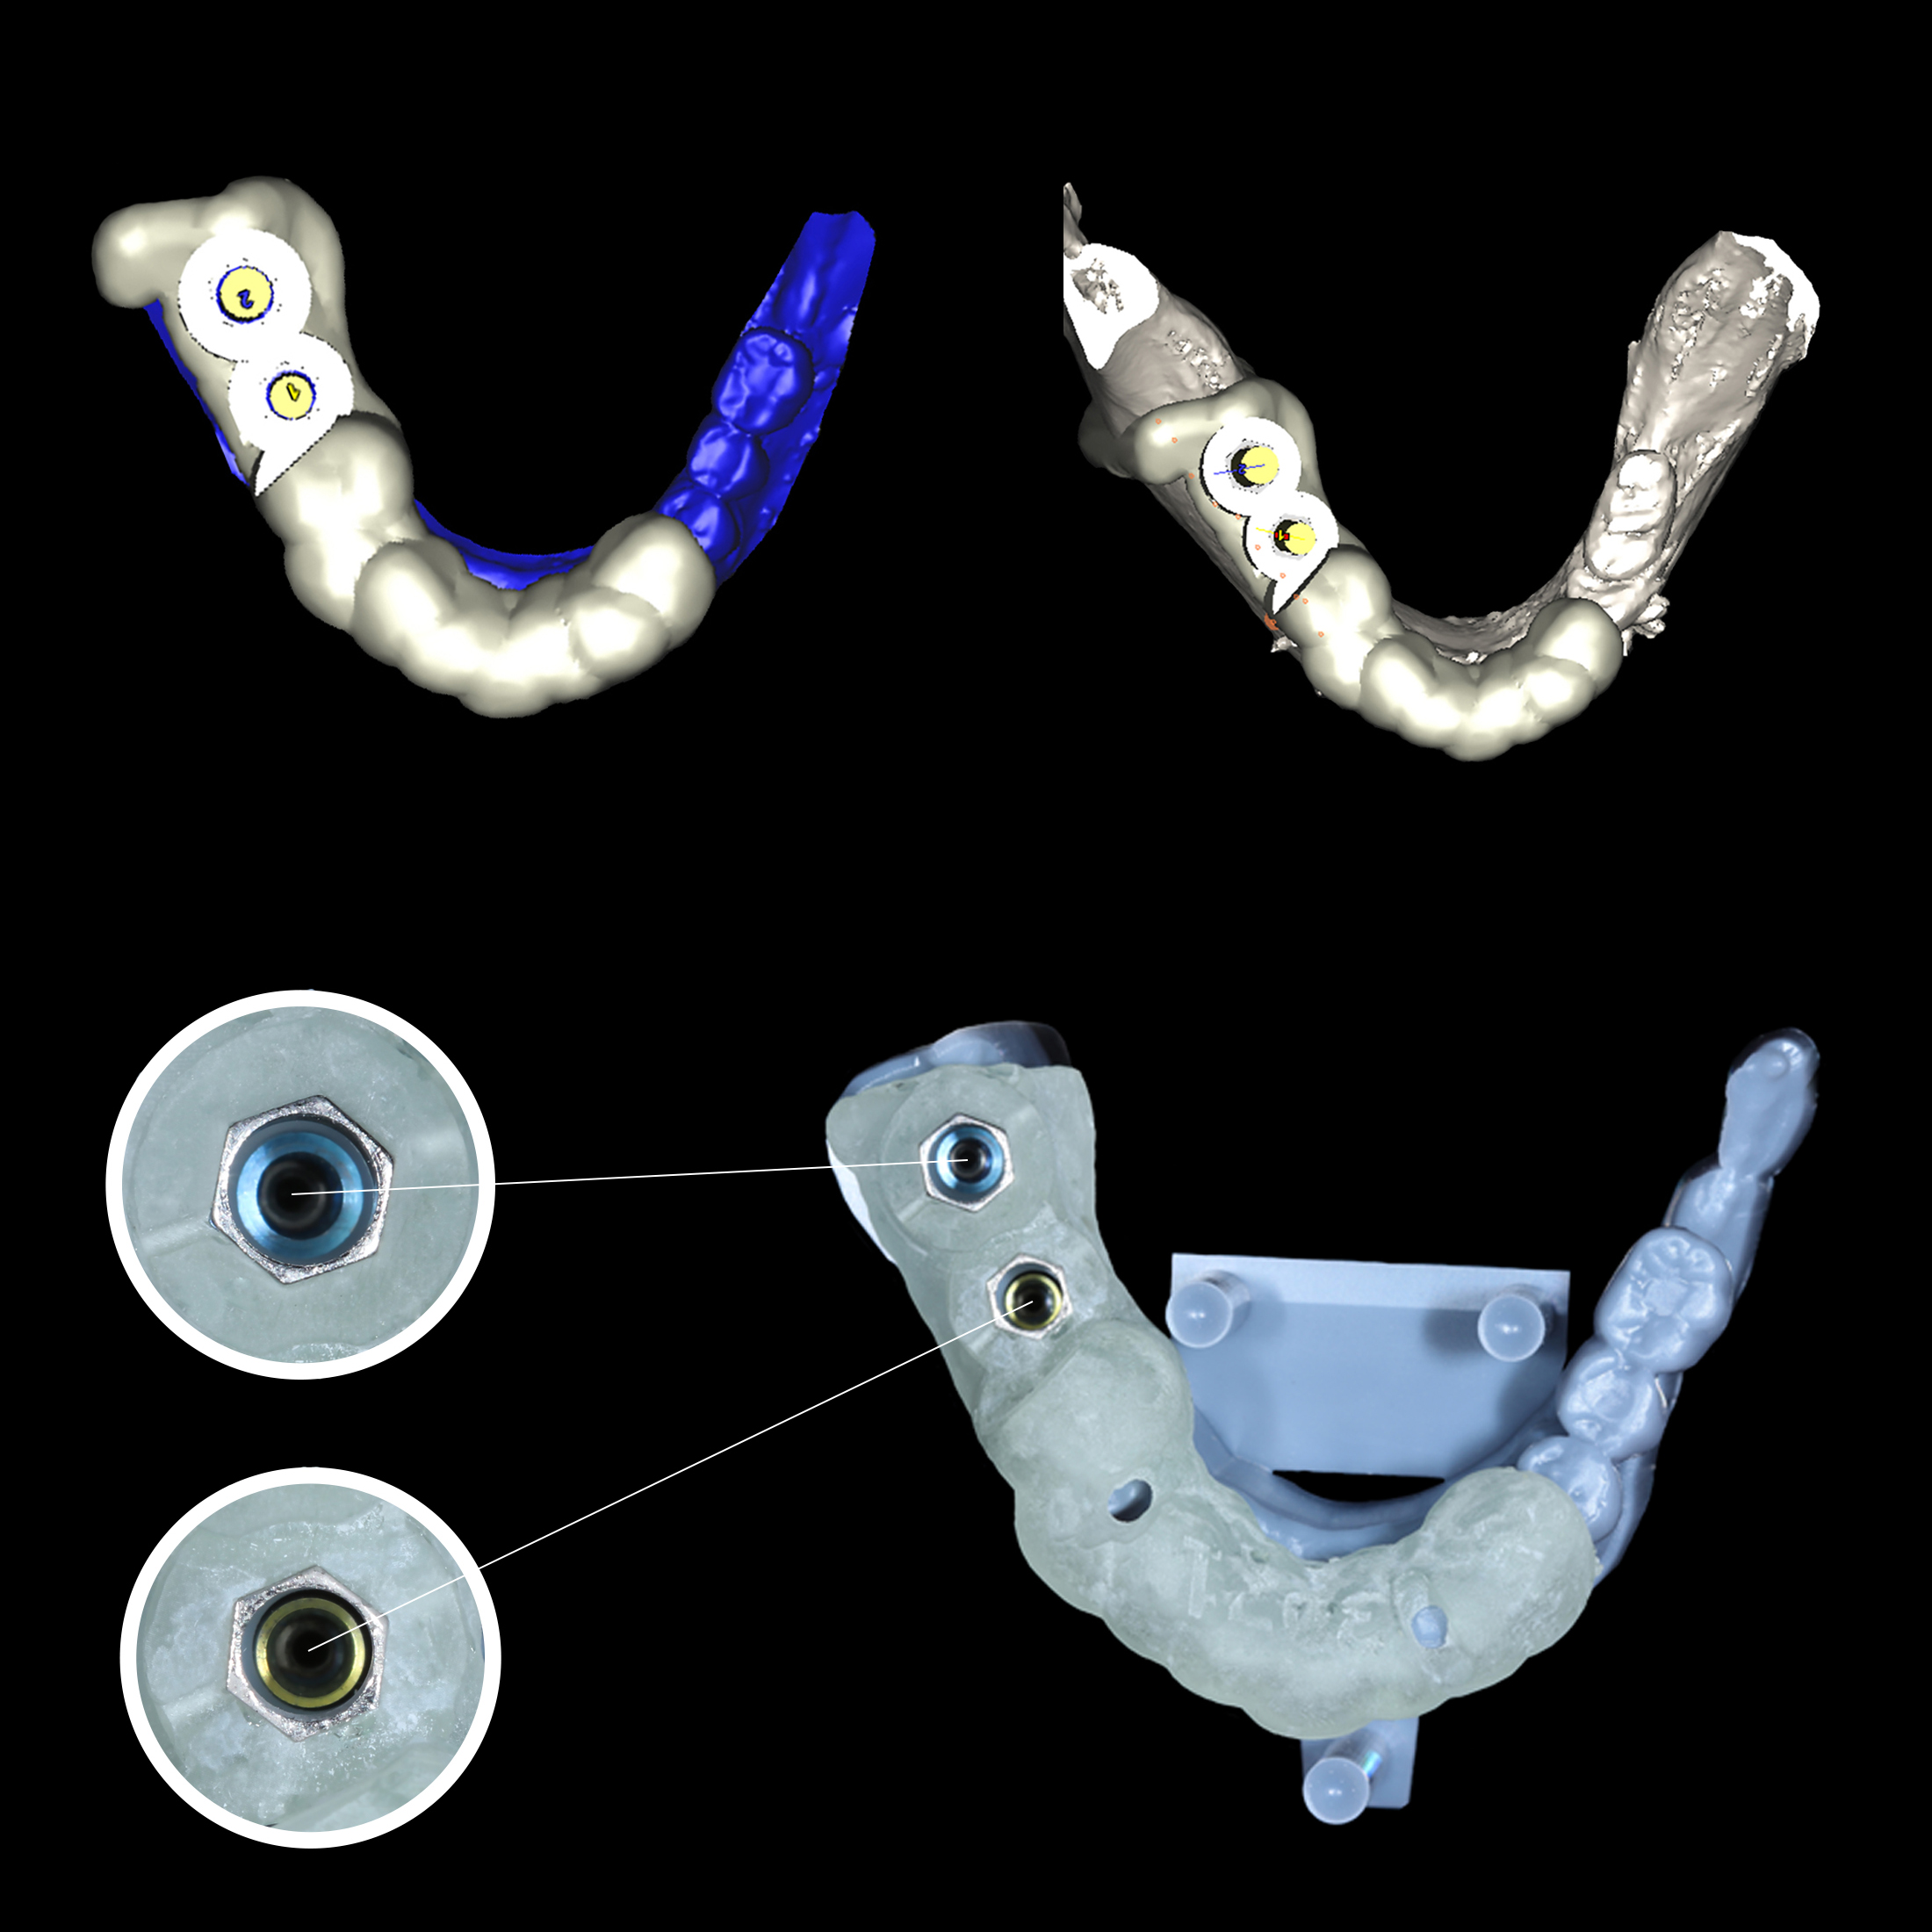

3D αξονική τομογραφία – Αριστερά: τρισδιάστατο μοντέλο του οστού της κάτω γνάθου με ψηφιακά τοποθετημένα τα δύο εμφυτεύματα.

Δεξιά: το ζωτικής σημασίας κάτω φατνιακό νεύρο και τα ψηφιακά ομοιώματα των εμφυτευμάτων. Η απόσταση από το νεύρο είναι επαρκής, επιτρέποντας την ασφαλή τοποθέτησή τους

Πάνω: Το ψηφιακό αρχείο του χειρουργικού νάρθηκα - Κάτω: Ο χειρουργικός νάρθηκας εκτυπωμένος από 3D εκτυπωτή